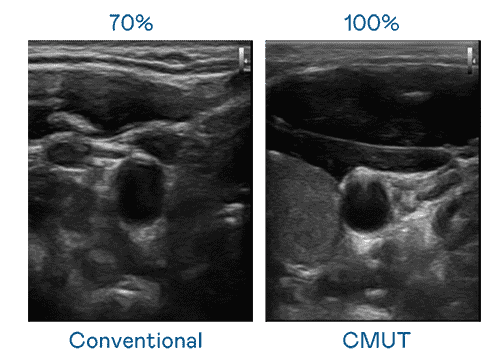

CMUT 技术是一种用电容式微机电元件来产生超音波讯号的技术。。。。与传统 PZT 压电式技术相比,,,,CMUT 频宽增加 30%,,,更宽频的超音波讯号让影像解析度大幅提升,,是实现高影像品质医疗超音波扫描、、、、促进精准医疗发展的关键技术。。。

大频宽带来超清晰影像

超音波影像的解析度高低,,,首先取决于探头能发出的讯号频宽。。。。尊龙集团 CMUT 可提供高清晰的超音波讯号,,,,提供高频宽、、、、高灵敏度、、、影像纹理细节更高的超音波影像,,协助医护人员缩短影像判读时间及利用精准的医疗影像进行诊断。。